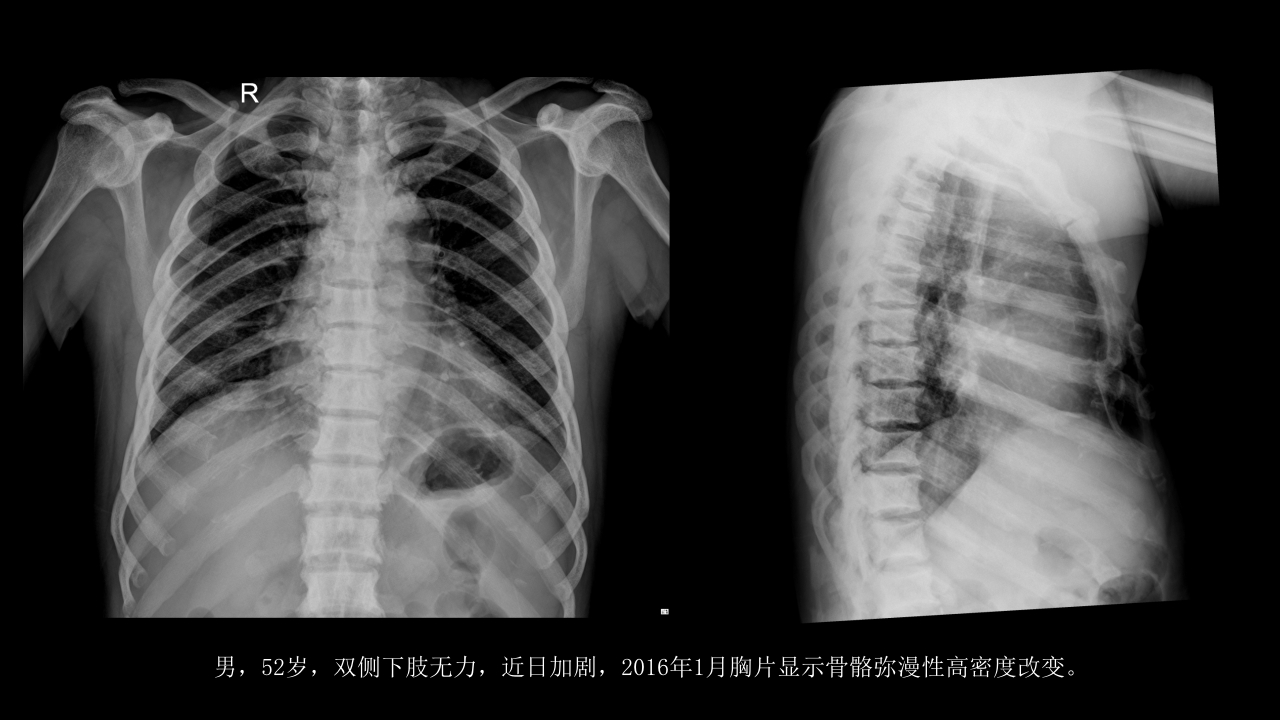

氟骨症的X线CT及MR影像及解读